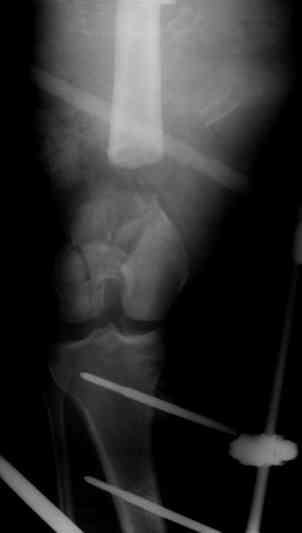

Больной с дефектом дистальной части бедра

Прошу совета, какую тактику избрать при лечении. Больной 27 лет, мотоциклист. Поступил 23.04.10

ДЗ. О. перелом н.з левого бедра Gustillo 3b (c повреждение бедренной вены), О.Правого бедра Gustillo 2, з. фрагментарный перелом левой голени. При поступлении Hb 66 ISS 40, Фиксация стержневыми аппратами, сосудистые хирурги выполнили шов вены. Выполена резекция бедренной кости 9 см.

На 7 сутки Желудочно-кмшечное кроветечение из стрессовых язв, 12 сутки флотирующий тромтоз 14 см установлен кава-фильтр.

На 15 сутки закрытие ран местными тканями. Раны заживают первично. Воспаления на стержнях нет.

В настоящий момент планируем. Переход со стержневых аппаратов на стержни с антибактериальным покрытием на правом бедре и левой голени.

Левое бедро планируем продолжить фиксировать в стержневом аппарате.

Вопрос: что делать с левым бедром? Учитывая внутрисутавной характер перелома, дефект бедра 9 см.